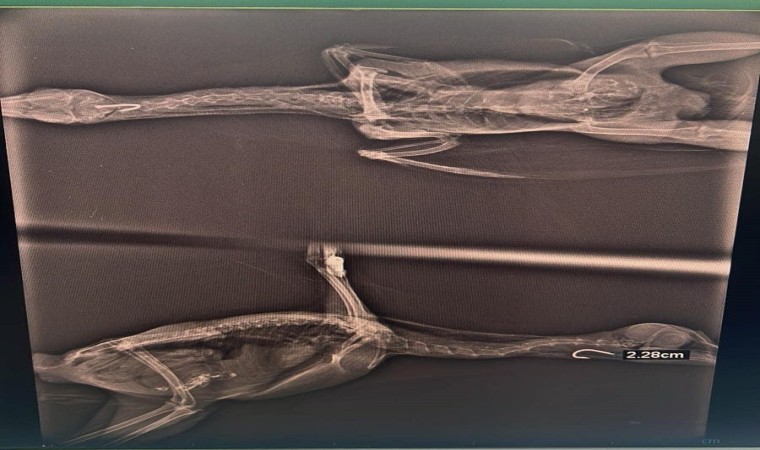

Yaralı anne saz tavuğu tedavisinin ardından yavrularına kavuştu. Misina ucu yutması sonucu tedavi altına alınan saz tavuğu, Doğa Koruma ve Milli Parklar Düzce Şube Müdürlüğü veteriner hekimlerince yapılan muayene sonucunda yutak bölgesinde tespit edilen misina ucu başarılı bir operasyonla çıkarıldı. Tedavisinin tamamlanmasının ardından Saz Tavuğu yavrularının olduğu ortama geri salındı.